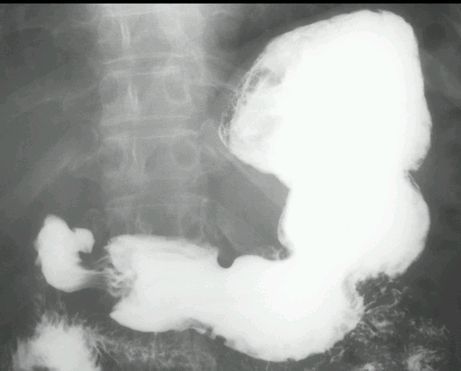

WRZÓD DWUNASTNICY

KONTRAST DO GOPP